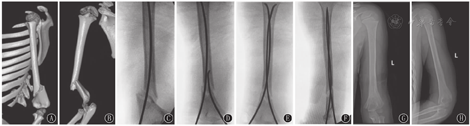

患儿均在术前完成X线正侧位、CT平扫+三维重建检查,了解骨折移位程度及有无隐裂,确切评估并排除血管神经损伤(图1)。体位:患者平卧于手术床,患肢均外展置于C形臂上。内固定方式均采用瑞士AO辛迪斯公司ESIN进行固定。

手术过程:首先根据透视选用直径合适的ESIN并预弯,以直径占肱骨内径30%左右为宜,若骨折断端处有隐性裂纹,建议进针点及进针方向均应稍偏离,并选用相对较细直径ESIN。依据骨折移位及斜面情况选择内/外侧进针点,ESIN接近骨折线时试行手法复位,透视证实复位成功时,调整针头方向,将ESIN打入骨折近侧。闭合复位失败者,改为切开复位。对于轻度粉碎骨折患儿,进针时合理设计进针方向,避开碎骨折块。手术成功后将ESIN贴骨面剪断(图1)。

14例患儿均顺利完成手术,闭合复位成功12例,切开复位2例。术中出血量20~55 mL,平均34.3 mL,平均手术时间37.5 min,平均外固定时间4.1周。术后随访10~27个月,平均18.4个月。术毕即时X线正位Baumann角(72.21±2.517)°,末次随访Baumann角(72.64±2.098)°,二者比较差异无统计学意义(t= 0.898,P>0.05)。患儿术后X线侧位肱骨前缘线均通过肱骨小头(图1)。末次随访根据Flynn评分标准评判优13例(92.9%),良1例(7.1%)。